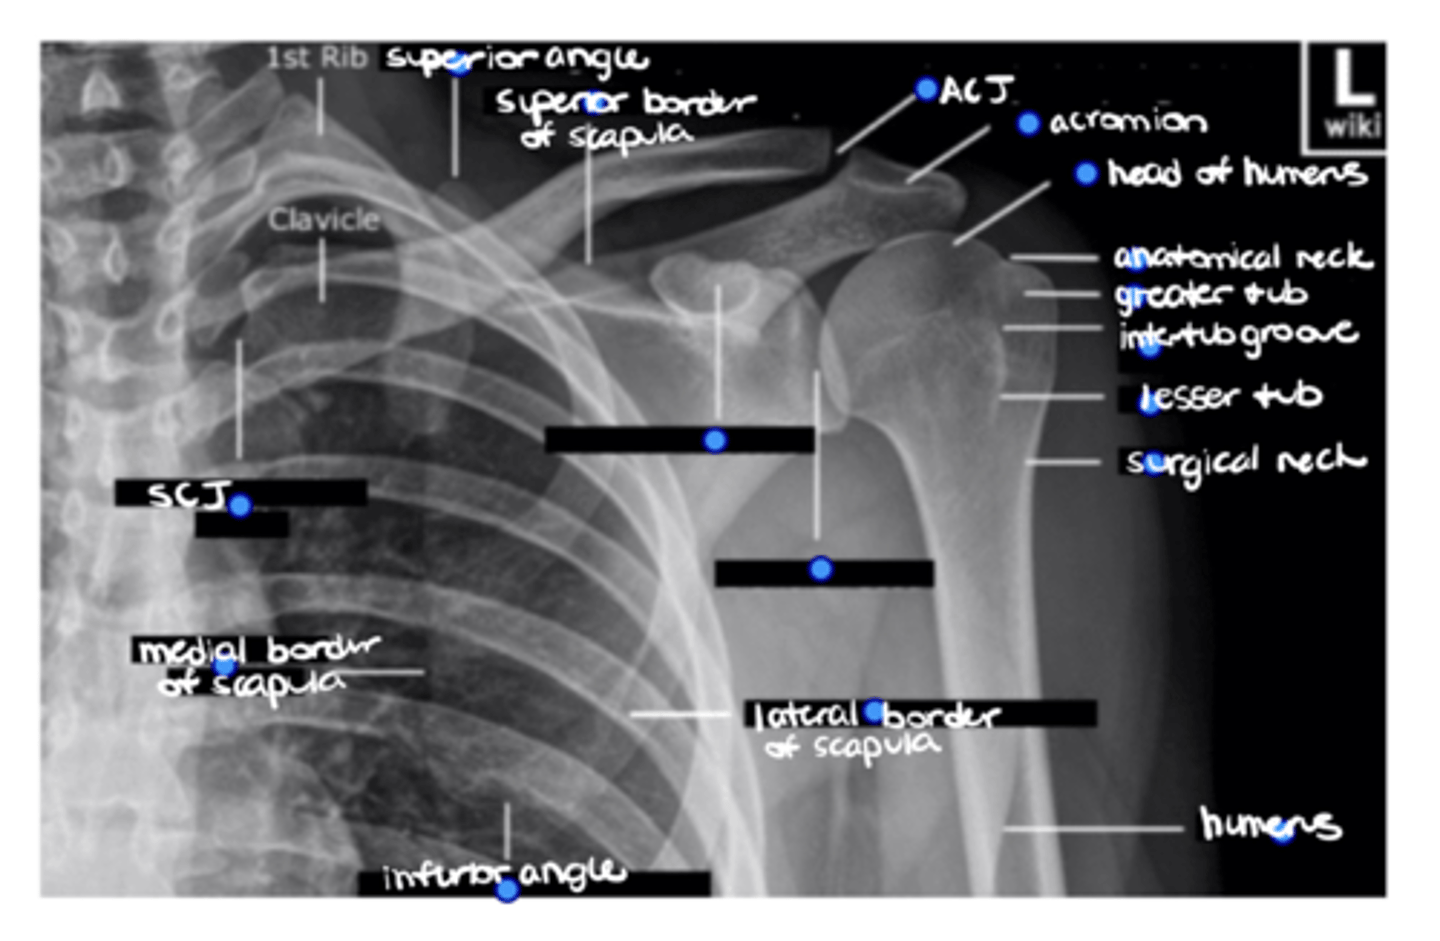

1. Coracoid process

2. Glenoid fossa

ID the 2 missing structures.